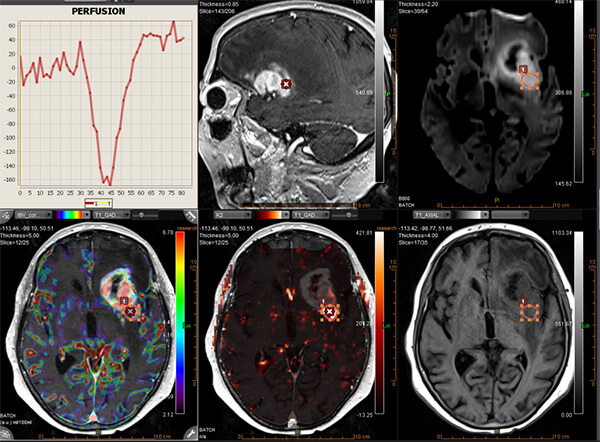

- Ειδικές τεχνικές state-of-the-art (Λειτουργική / Πολυπαραμετρική MRI, Φασματοσκοπία, Δεσμιδογραφία, Δυναμικές Αγγειογραφίες, Νευρογράφημα, Μελέτη Ροής ΕΝΥ)

- Συνδυασμός των ειδικών τεχνικών με ανατομικές εικόνες υψηλής ευκρίνειας, ο οποίος δίνει σημαντικές επιπρόσθετες πληροφορίες για τον χαρακτηρισμό του ιστού (αριθμό των κυττάρων, αιματική ροή και μεταβολική δραστηριότητα)

- Perfusion (τεχνικές DSC, DCE, ALS)